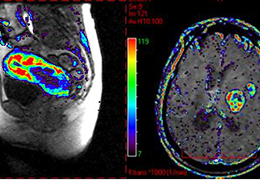

DCE-MRI permeability map color overlay on MRI in cervical cancer (left) and brain tumor (right). Data courtesy of Dr Nick Ferris, Peter MacCallum Cancer Center, Australia.